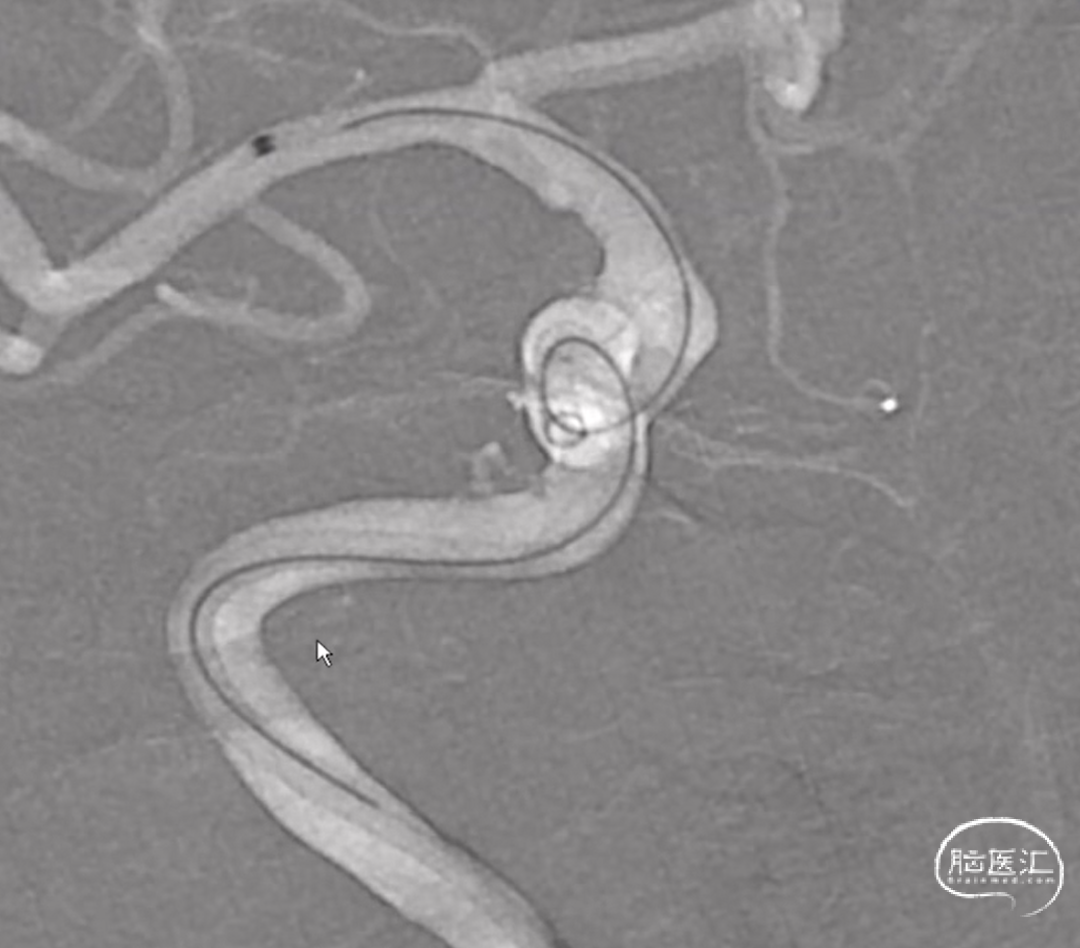

治疗过程

术前3D造影

建立通路,右股动脉穿刺置动脉鞘,经动脉鞘送入6F长鞘套接6F 115cm 通桥银蛇®颅内支持导管超选至左侧颈内动脉C5段,并在微导丝引导下将支架导管超选至左侧大脑中动脉M1段。

释放通桥麒麟™血流导向密网支架 4.0*20mm。

导丝按摩

术后造影,确认通桥麒麟™血流导向密网支架贴壁。

术后3D造影